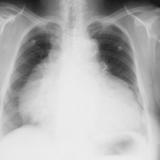

Case 7a

Peric effusion

Date: 02/25/2013

Views: 3031